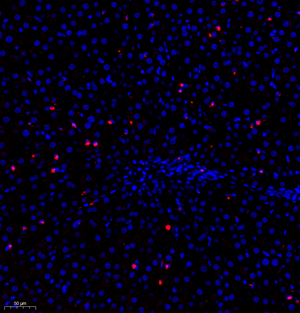

| IF analysis of MPO (GB11224). Sample: Mouse lung+lps (Paraffin), 4% PFA (G1101) 12-24h. Antigen retrieval: TE buffer (pH 9.0) (G1203),98°C,20min. Blocking buffer: 3% BSA in PBS (GC305010), RT, 30min. Primary antibody: 1: 1200, 4°C overnight. Secondary antibody: Cy3 conjugated Goat Anti-Rabbit IgG (H+L) (GB21303), 1: 300 RT, 1h. |

| IF analysis of MPO (GB11224). Sample: Mouse spleen (Paraffin), 4% PFA (G1101) 12-24h. Antigen retrieval: TE buffer (pH 9.0) (G1203),98°C,20min. Blocking buffer: 3% BSA in PBS (GC305010), RT, 30min. Primary antibody: 1: 1200, 4°C overnight. Secondary antibody: Cy3 conjugated Goat Anti-Rabbit IgG (H+L) (GB21303), 1: 300 RT, 1h. |

| IF analysis of MPO (GB11224). Sample: Rat liver+lps (Paraffin), 4% PFA (G1101) 12-24h. Antigen retrieval: TE buffer (pH 9.0) (G1203),98°C,20min. Blocking buffer: 3% BSA in PBS (GC305010), RT, 30min. Primary antibody: 1: 1000, 4°C overnight. Secondary antibody: Cy3 conjugated Goat Anti-Rabbit IgG (H+L) (GB21303), 1: 300 RT, 1h. |